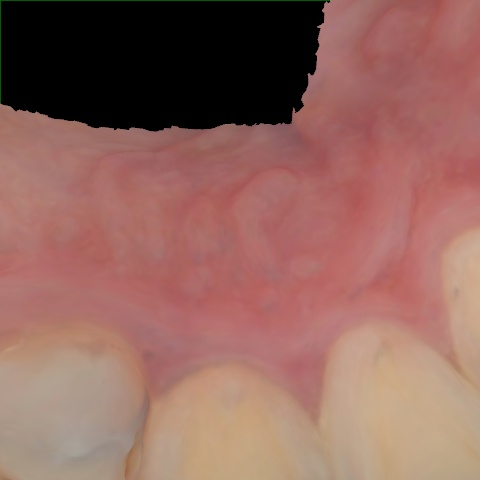

NHD39990

Annotated as "Good"

Original Image Rendering Image